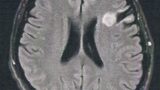

・画像上は神経膠腫(グリオーマ)のグレード2と思われる。

・低悪性度である。(良性ではない)

- The MRI image shows that the tumor seems to be a glioma of grade 2.

- It is a low malignant tumor. But it is not a benign tumor.